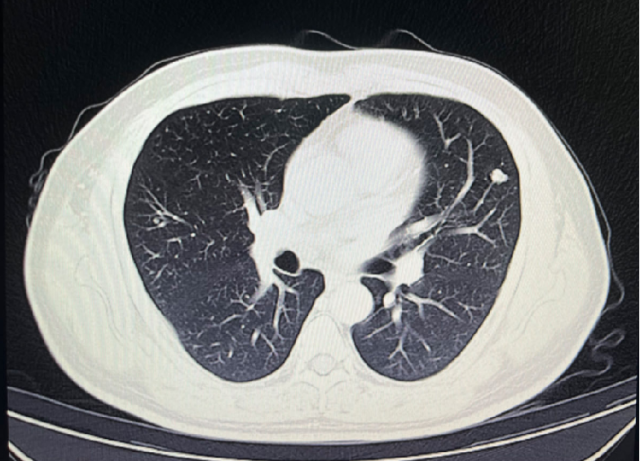

影像学检查

2023-05-03: